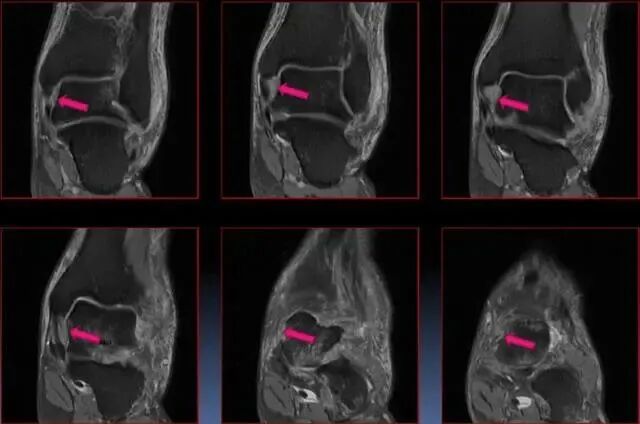

距骨在踝穴内有无倾斜,会通过影响关节面接触面积而影响关节所受应力的大小。有轻度倾斜,关节面所受到的应力会因为承重面积变小而明显增加。

Ⅰ度:ATFL损伤;

Ⅱ度:ATFL+CFL损伤;

Ⅲ度:ATFL+CFL+PTFL损伤。